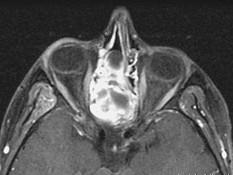

问题 15岁,男性,渐进性鼻塞1年余,MRI扫描如图所示,请选择最可能诊断 ( )

选项 A、鼻咽部囊肿 B、鼻咽癌 C、鼻咽部脓肿 D、脊索瘤 E、鼻咽部纤维血管瘤

答案 E